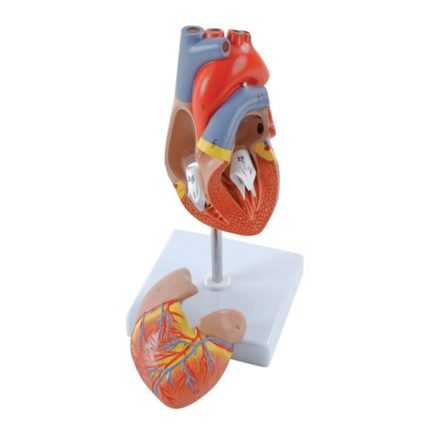

Modèle anatomique de coeur humain TND 164,000 Le prix initial était : TND 164,000.TND 124,000Le prix actuel est : TND 124,000. TTC

Réf: KL_448692